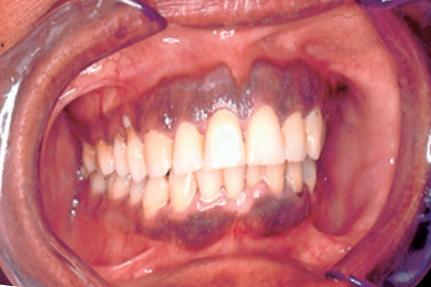

Manchas

São alterações de cor da mucosa ou pele, uniformes e sem relevo, podendo variar desde colorações mais claras, brancas até as mais enegrecidas, amarronzadas e arroxeadas, dependendo do tipo de pigmento. Não apresentam tamanho definido, podem ser puntiformes ou atingirem alguns centímetros (Fig. 1-1).

Exemplos: melânicas (pigmentos endógenos [Fig. 1-2], e exógenos [Fig. 1-3]), hemáticas (vasculares e hemorrágicas [Fig. 1-4]).

Vale lembrar que, classicamente, para as manchas secundárias devemos denominá-las de mácula, como por exemplo as manchas melânicas (Fig. 1-5) e eritematosas após trauma.